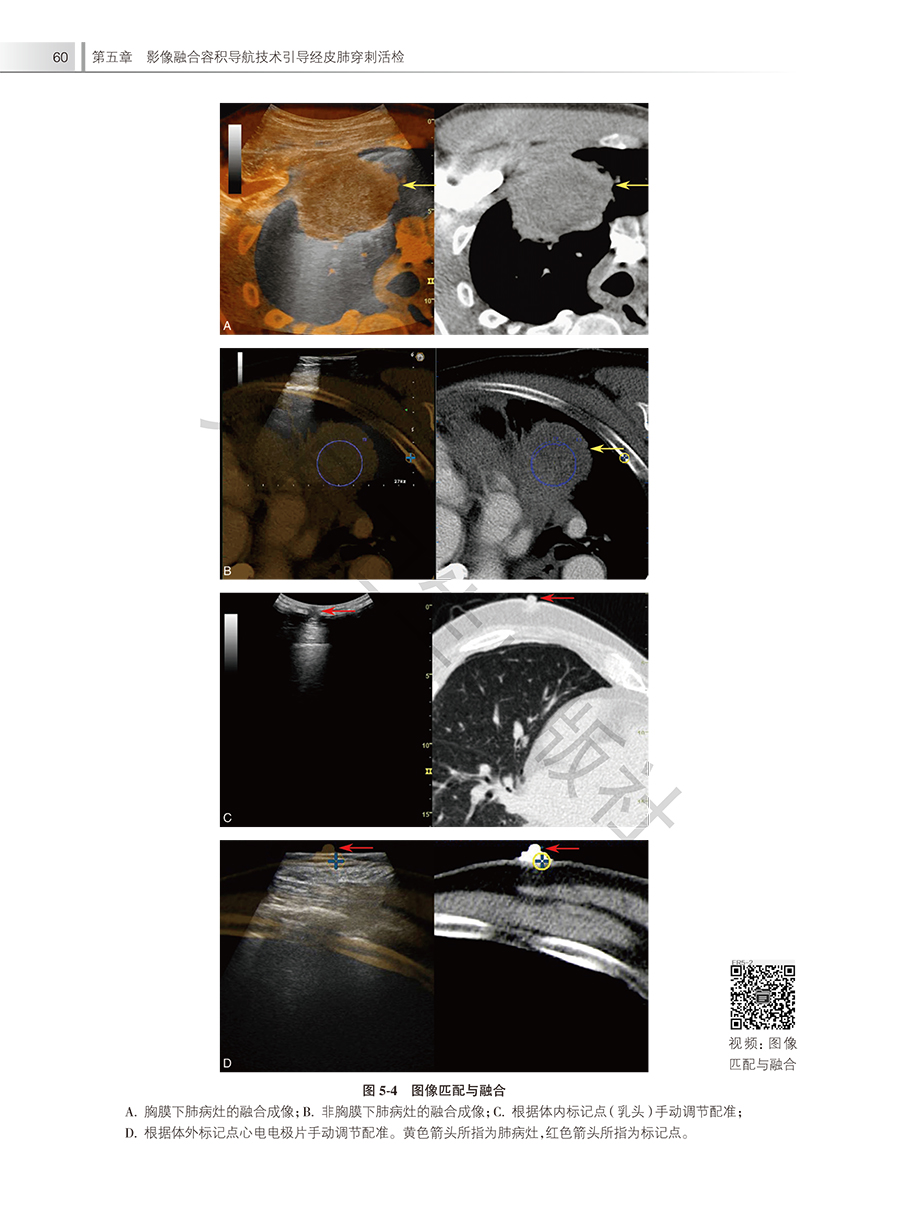

本书由上海市肺科医院超声科主任王茵教授牵头,带领相关领域专业人员,在总结现有指南和专家共识基础上,结合临床工作实践与科研成果编写。书中聚焦超声引导经皮肺活检,结合大量的临床案例,详尽介绍了肺穿刺活检的发展、超声引导经皮肺活检的适应证与禁忌证、术前准备、操作流程、术后观察及并发症处置、随访管理等,配以大量精美图片和超声视频,内容全面、清晰易懂。本书能够帮助读者加深对超声引导经皮肺穿刺活检的理解,为临床实际应用提供可借鉴的依据。